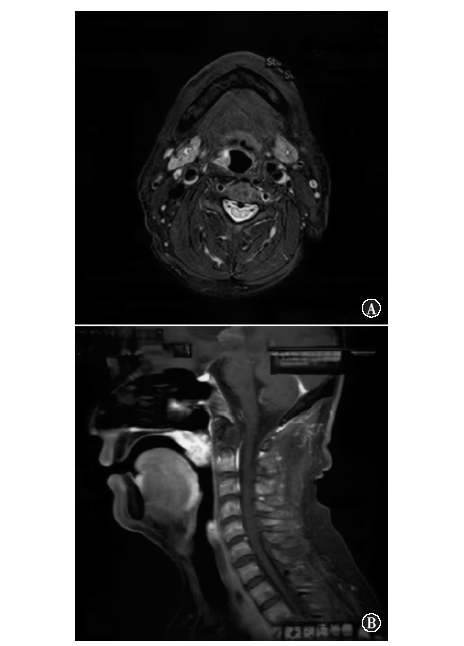

软腭及食管多原发鳞状细胞癌鼻尖皮肤转移1例

多原发鳞状细胞癌发生鼻尖皮肤转移极为罕见,文献报道较少,且鳞状细胞癌病理表现相似,较难诊断。现回顾性分析1例软腭及食管多发鳞状细胞癌出现远处鼻尖皮肤转移患者的临床资料,结合相关文献复习,以提高对本类疾病的认识。